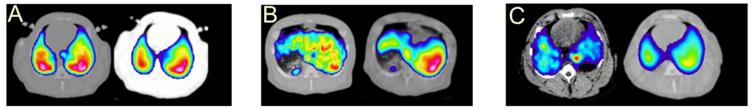

Current status and directions of 68Ga-based imaging agent development

68Ga-based imaging agents comprising small molecules, large biomolecules, and particles have been explored for the imaging and quantitation of various physiological disorders and biological functions. The molecular imaging of oncological diseases have been investigated most extensively targeting receptors (e.g. G-protein coupled receptor family and human epidermal growth factor receptor (HER) family, folate and urokinase receptors), enzymes, antigenes as well as visualizing downstream biological processes such as angiogenesis, hypoxia, proliferation, apoptosis, glycolysis. Probes for non-targeted imaging of pulmonary and myocardial perfusion and ventilation as well as targeting imaging of inflammation, infection, and mRNA have also been considered and fundamental exploration is ongoing.

Oncological application

Various approaches have been developed for the imaging of certain biological processes involved in cancer diseases with receptor imaging being most thoroughly investigated. There are currently few 68Ga-based imaging agents in routine clinical practice and clinical studies however the number of applications is increasing with acceleration. Somatostatin analogues are already established in clinical routine. Imaging feasibility of GRPR, GLP-1R, MSH, HER2 as well as prostate-specific membrane antigen, osteoblastic bone metastases, amino acid uptake, glucose transport, angiogenesis has been clinically demonstrated in patients [7, 40, 141-145]. Extensive basic research is conducted on the development of 68Ga-based probes for the imaging of CCK, CXCR, MSH, gonadotropin releasing hormone (GnRH), NT, folate, integrin, vascular endothelial growth factor (VEGF), urokinase receptors as well as enzymes, antigens, and multidrug resistance (MDR1) P-glycoprotein (Pgp). Imaging probes for visualizing such processes in tumours as proliferation, apoptosis, hypoxia, glycolysis, and angiogenesis as well as bone metastases have also been investigated. A number of particulate agents have been developed for the delivery of imaging reporters or therapeutic agents to the tumour target.